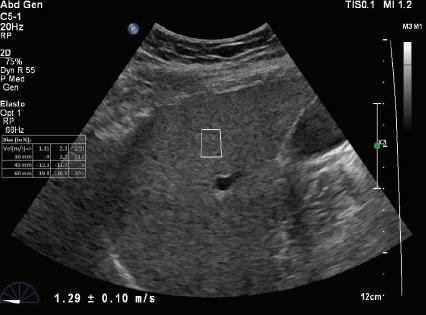

FIG. 1.24 Shear Wave Elastograms of (A) Normal and (B) Cirrhotic Liver. Shear wave velocities measured in liver tissue samples by shear wave elastography indicates a velocity of 1.29 ± 0.10 m/sec in the normal liver compared to a velocity of 4.41 ± 0.17 m/sec in the cirrhotic liver. Increased shear wave velocity is associated with increased tissue stiffness due to hepatic fibrosis. (Courtesy of P. O’Kane, Thomas Jefferson University.)

A - Normal liver

v = 1.29 ± -.10 m/s

B - Cirrhotic liver

v = 4.41 ± -.17 m/s